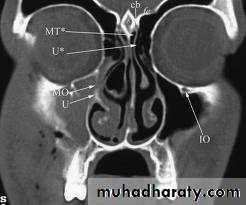

Ostiomeatal Complex

Ostiomeatal complex is that area under the middle meatus (airspace) into which the anterior ethmoid, frontal and maxillary sinuses drain.

Ostiomeatal complex is the functional relationship between the space and the ostia that drain into it